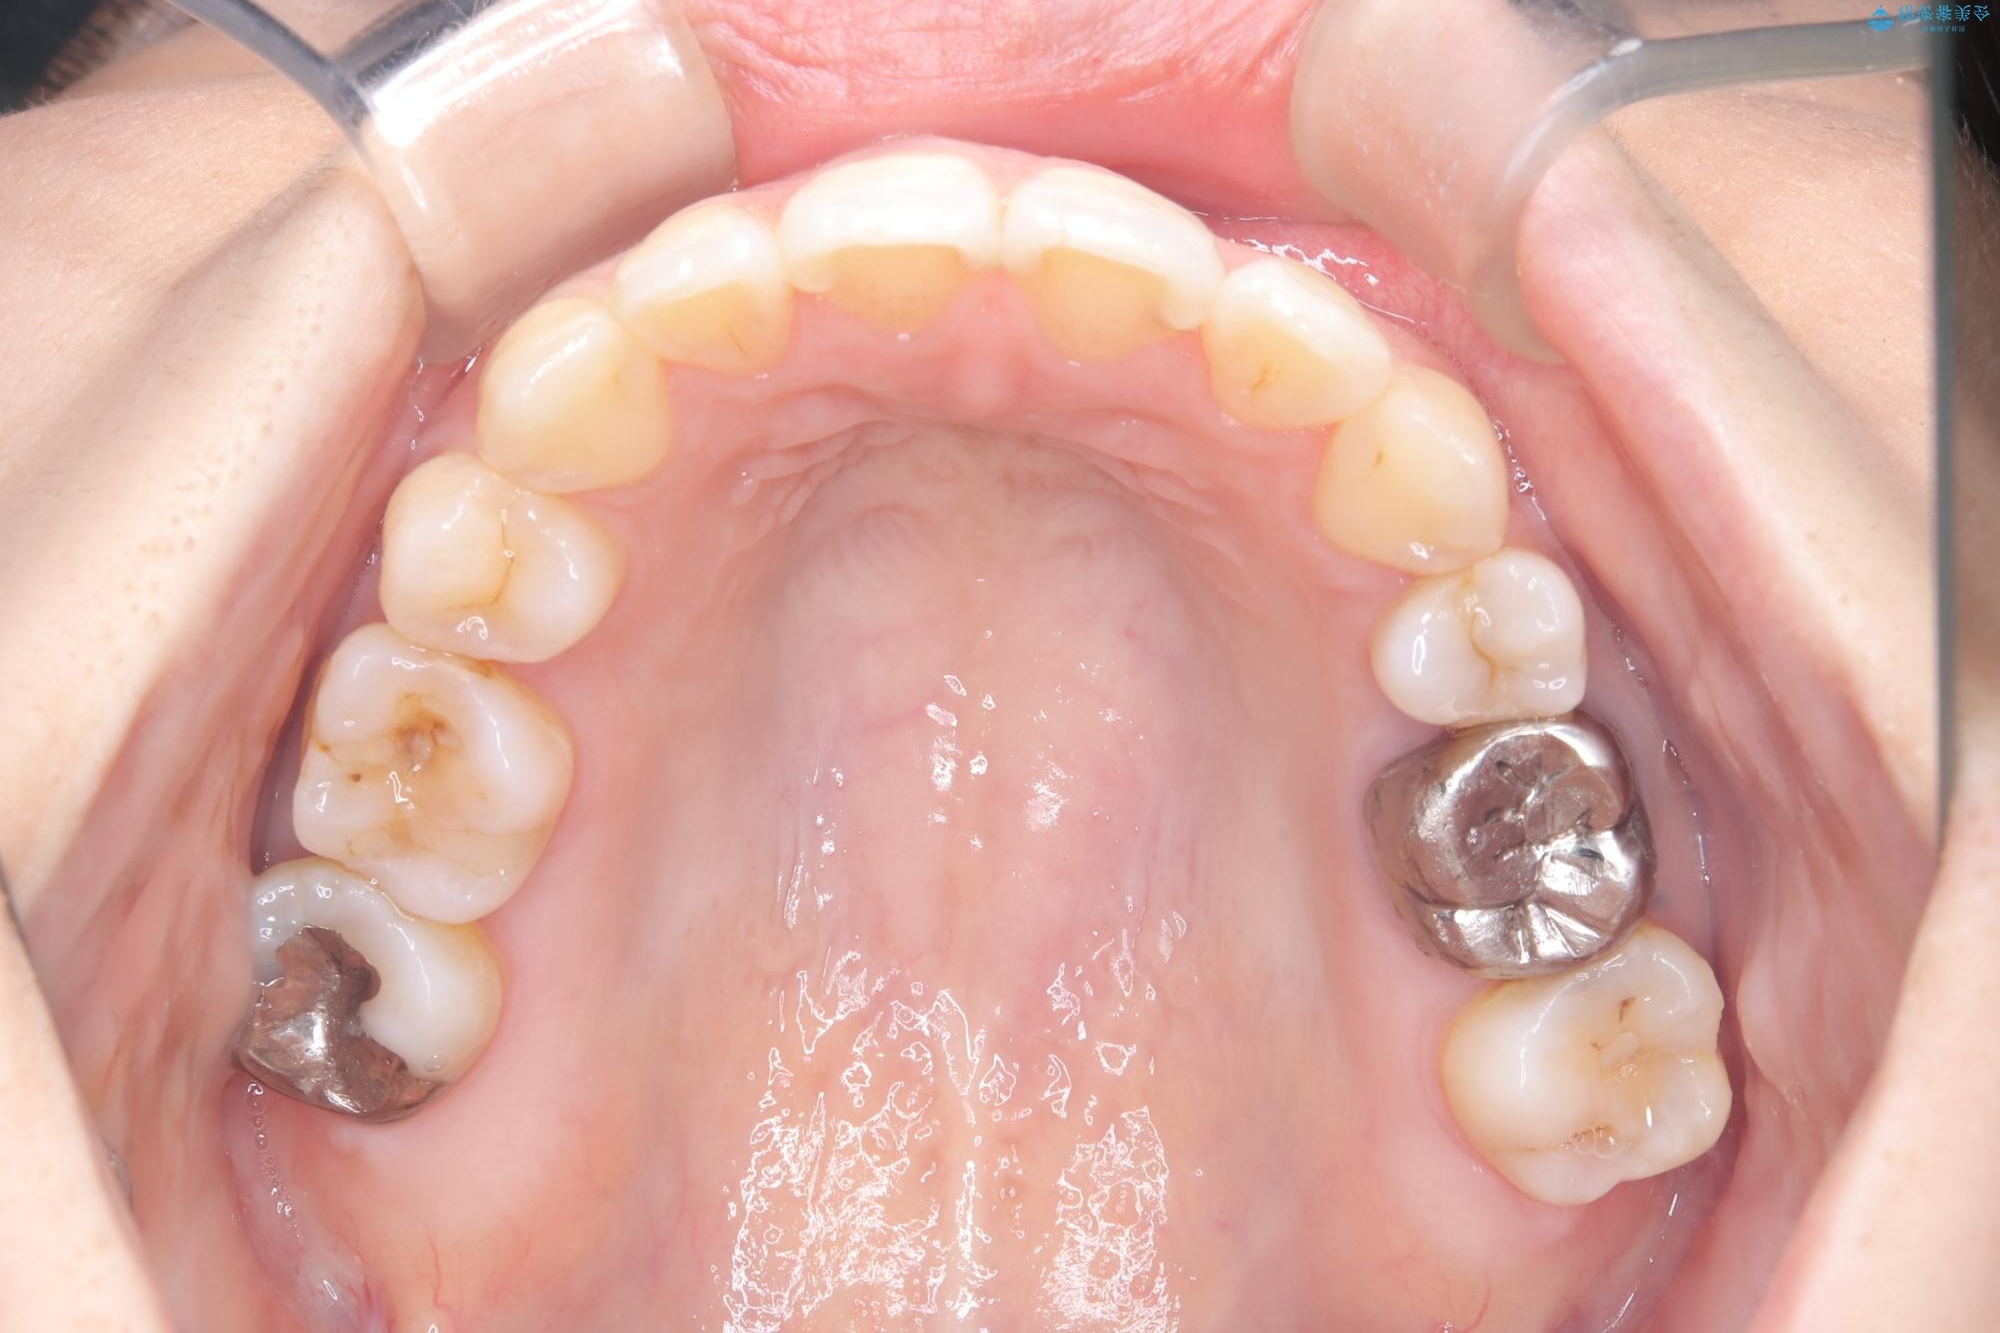

右側第二小臼歯、左側第一小臼歯、下顎両側第一大臼歯を抜歯しワイヤ-矯正を行いました。

骨格的顎の変位を認めたため、顔貌に対しピッタリ上下の歯の正中を合わせることは難しいと説明し、上下左右計4本小臼歯を抜歯しワイヤー矯正治療を行いました。